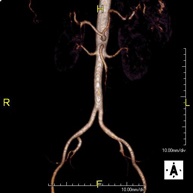

Prueba diagnóstica no invasiva que consiste en el estudio vascular del sector aorto-ilíaco y de los vasos arteriales de ambas extremidades inferiores, obteniendo imágenes de alta definición anatómica mediante el empleo de un campo electromagnético y ondas de radio (con un emisor y un receptor). Es indispensable el uso de contraste paramagnético (Gadolinio). Sin embargo, no utiliza radiación ionizante. La calidad de las imágenes permite realizar reconstrucciones en 2D y 3D. Está especialmente indicado en aquellos pacientes en los que hay sospecha de enfermedad vascular de ambas extremidades, en pacientes con enfermedad vascular de ambas extremidades como el mapa vascular antes del tratamiento (percutáneo o quirúrgico), como el mapa vascular pre-quirúrgico en pacientes con lesiones óseas o musculares que requieran cirugía, etc. - Angio-RM Arterias renales

Prueba diagnóstica no invasiva que consiste en el estudio de la arteria aorta abdominal, obteniendo imágenes de alta definición anatómica mediante el empleo de un campo electromagnético y ondas de radio (con un emisor y un receptor). Es indispensable el uso de contraste intravenoso paramagnético (gadolinio). Sin embargo, no utiliza radiación ionizante. La calidad de las imágenes permite realizar reconstrucciones en 2D y 3D. Está especialmente indicado en aquellos pacientes en los que hay sospecha de enfermedad vascular de ambas extremidades, en pacientes con enfermedad vascular de ambas extremidades como mapa vascular antes del tratamiento (percutáneo o quirúrgico), como mapa vascular pre-quirúrgico en pacientes con lesiones óseas o musculares que requieran cirugía… - Soft tissue lesion MRI angiography